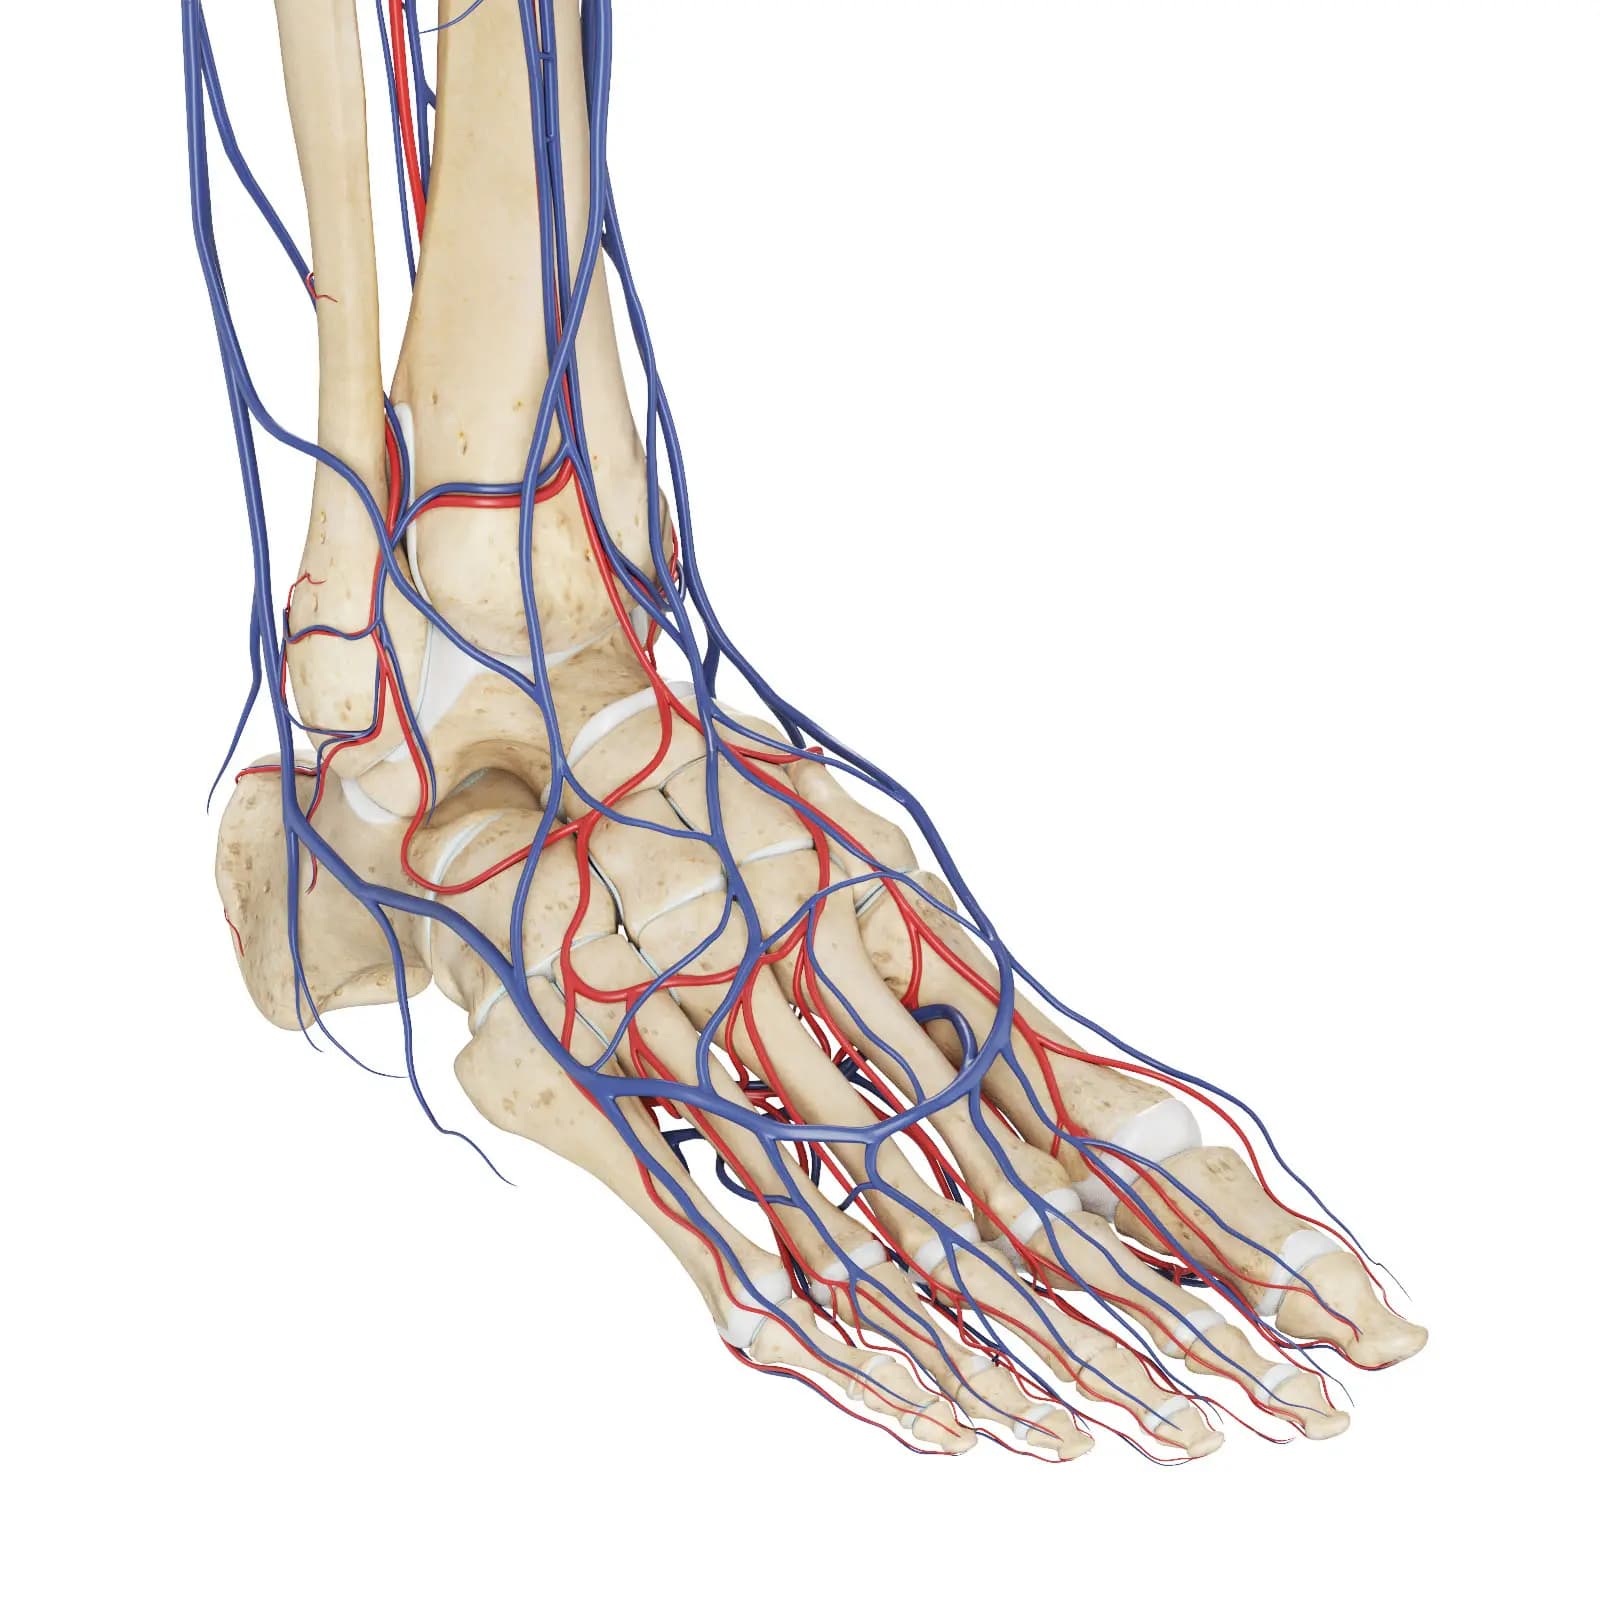

3d Rendered Medical Illustration Of The Vascular System Of The Foot

3d Rendered Medical Illustration Of The Vascular System Of The Foot